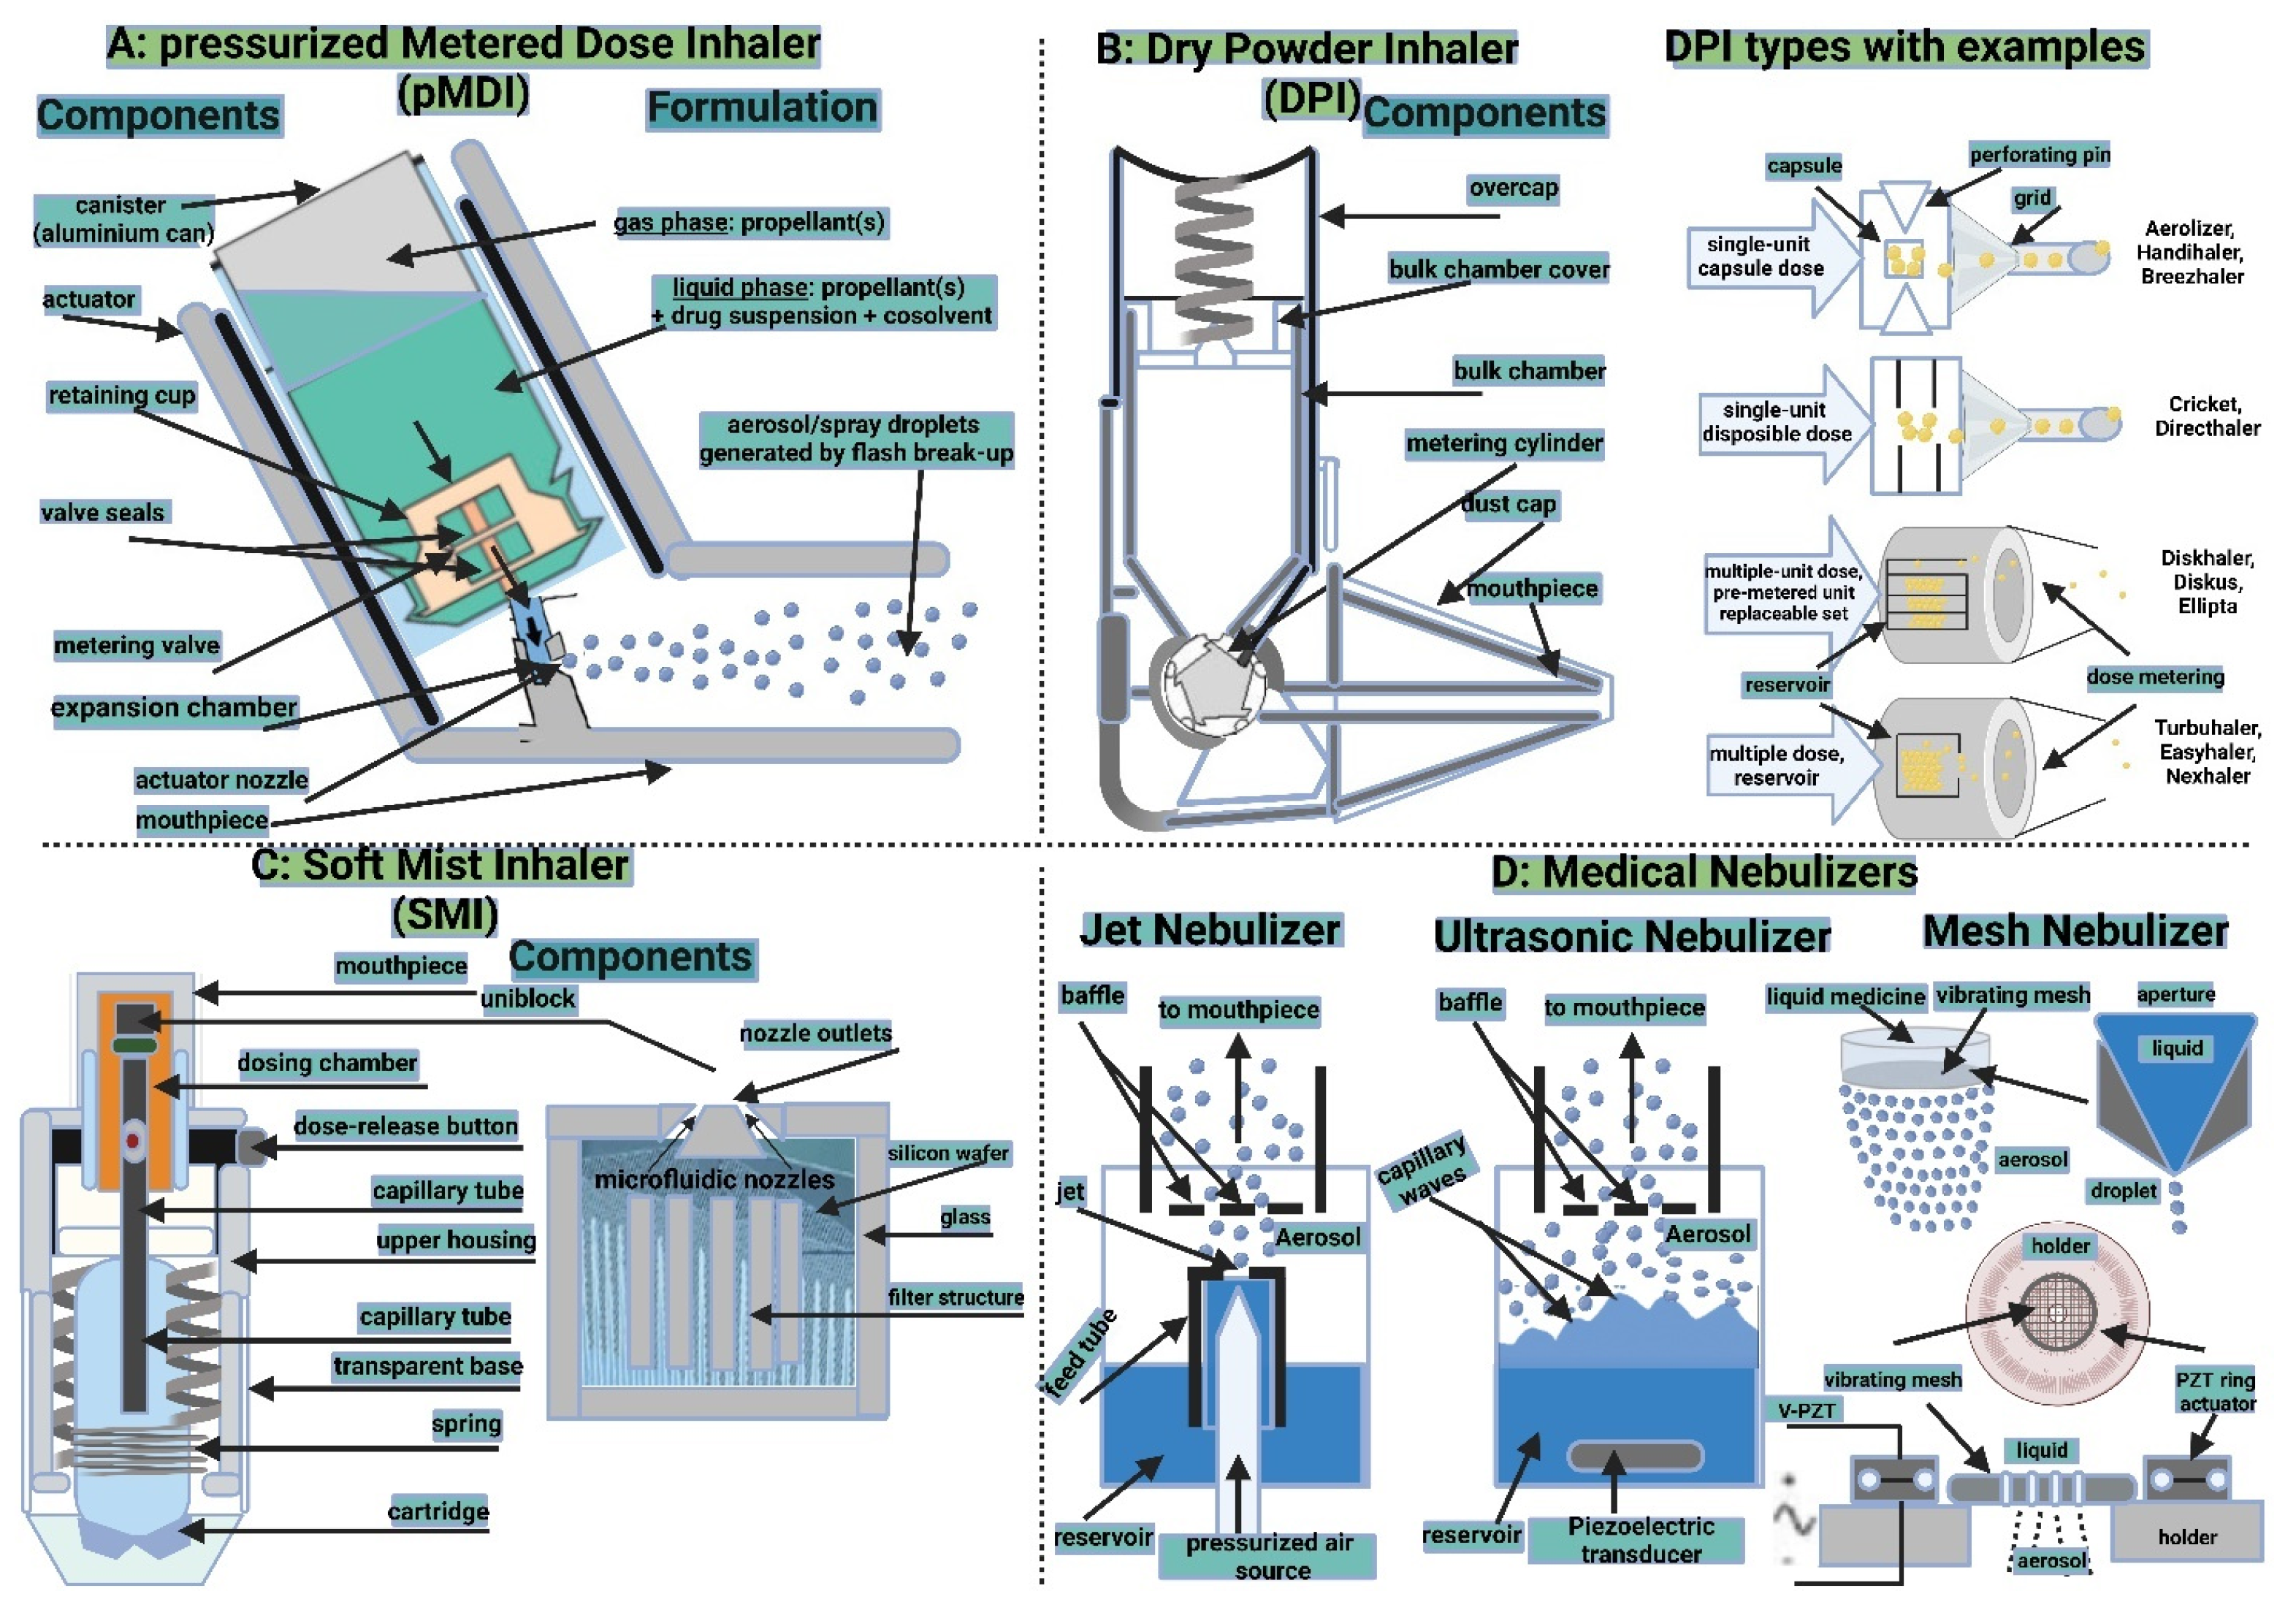

5.2.2. Inhalation Drug Delivery Devices

Pressurized Metered-Dose Inhalers

Dry Powder Inhalers

Soft Mist Inhalers

Medical Nebulizers